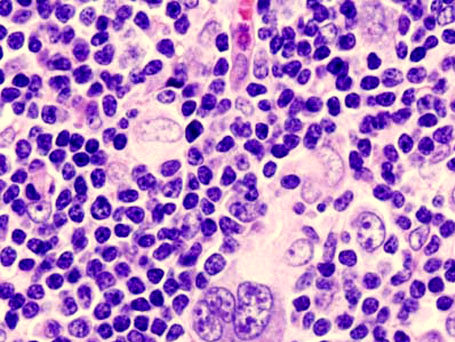

Лимфомами называется группа заболеваний онкологического характера, при которых поражается лимфоидная ткань. Специалисты выделяют большое множество разновидностей лимфом, которые различаются по иммуногистохимическим критериям и требуют различного подхода к терапии.

Виды лимфом

Все злокачественные заболевания лимфатической ткани лимфомы разделяют на 2 большие группы:

- лимфома Ходжкина (лимфогрануломатоз) – составляет 20% от общего числа лимфом;

- неходжкинские лимфомы, включающие до 30 видов.

Название первой группы произошло от имени английского онкогематолога Томаса Ходжкин, посвятившего этому заболеванию много научных работ. Этот вид лимфомы характеризуется более изолированным поражением лимфатических узлов, менее агрессивным и медленным развитием заболевания, и считается сегодня практически полностью излечимым.Все остальные лимфомы, отличающиеся от лимфогрануломатоза более агрессивным характером, объединены в группу неходжкинских лимфом (НХЛ). Они характеризуются системным поражением лимфоузлов и всех органов, быстрым клиническим развитием, тяжёлым состоянием пациентов.

Неходжкинские лимфомы разделяют на Т-клеточные и В-клеточные, в зависимости от того, какой вид лимфоцитов заболевает. Каждый из них, в свою очередь, включает различные подвиды лимфом: